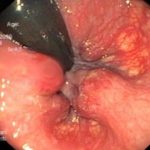

Как выглядит внутренний геморрой

Внутренний геморрой (фото 1) для многих пациентов становится неприятным сюрпризом – вроде бы предпосылок для развития заболевание нет, но начальная стадия геморроя и чувство дискомфорта при дефекации не дают людям покоя. Начальная стадия внутреннего геморроя проявляется следующими симптомами:

- болезненность и дискомфорт при дефекации – первые признаки, с которыми сталкиваются пациенты. Сила болевых ощущений у каждого человека различна, это зависит от наличия таких осложнений, как анальные трещины и т.д. Некоторые пациенты и вовсе не ощущают признаков геморроя;

- если шишки внутреннего геморроя существенно увеличены, то они могут выпадать наружу, хотя потом и прячутся. Сразу после дефекации можно прощупать шишки, ущемленные сфинктером анального отверстия;

- жжение и зуд при дефекации становятся постоянными спутниками пациентов, поскольку происходит постоянное раздражение прямой кишки.

Кровь при внутреннем геморрое появляется на третьей и четвертой стадии развития заболевания. Обычно в это время боль усиливается, шишки выпадают все чаще, поэтому сомнений в наличии геморроя не возникает.